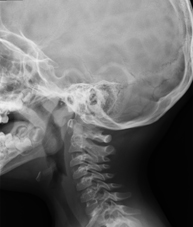

- RX Columna cervical

Tècnica que usa els raigs X a través de la qual s'obtenen imatges de la columna cervical per al seu estudi. Indicacions: traumatisme, dolor cervical. - RX Columna dorsal